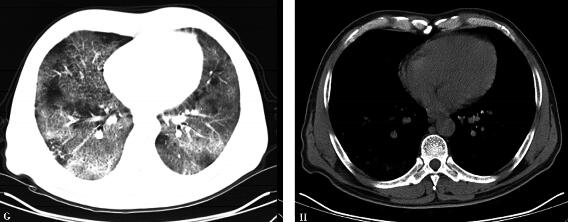

患者未能定期随诊,直至出院后3个月(2010年7月5日)才首次复查胸部CT(图2),结果提示:双肺病变进展,双肺野透光度进一步降低,双肺野背侧部分肺组织实变,肺野内小叶间隔明显增厚,伴磨玻璃阴影,出现典型的“铺路石征”。

图2

评价:规范应用糖皮质激素治疗3个月,复查CT示双肺病变进展,并出现“铺路石征”,故重新审视诊断思路是当务之急。仅靠胸部影像学及病史特点,在未能获取病理资料情况下确定间质性肺疾病的类型是导致诊疗失败的关键。

评价:患者明确诊断“PAP”。回顾患者诊治过程,除外患者拒绝完善必要的辅助检查(纤维支气管镜)的自身因素,从临床角度审视,关键在于单方面重视影像学的进展,而没有联系患者的具体情况,忽视了一个非常重要的问题:临床表现与影像学结果不平行,尽管规范治疗后胸部影像学进行性进展,但患者活动耐量尚可,可自行爬2层楼,肺部阳性体征不明显,这是PAP的特征之一。其次,过分重视吸烟在间质性肺疾病分型中的地位并过分相信“院外口服激素症状好转”的信息,也是延误诊治的原因之一。第三,患者入院前治疗过程中症状曾好转,其原因可能与病程中合并感染,抗感染治疗有效有关,误认为与激素治疗有关,从而使诊治思路偏离正常轨道。最后,关于不同类型间质性肺疾病影像学识别欠斟酌:仔细分析图55-2的相关影像学特征,除双肺弥漫的磨玻璃影向肺野中内带进展外,局部已出现“铺路石样”改变,却误认为“网格影”。